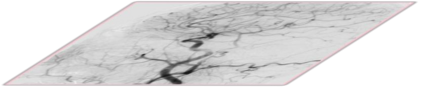

The rapid and accurate direct multi-frame interpolation method for Digital Subtraction Angiography (DSA) images is crucial for reducing radiation and providing real-time assistance to physicians for precise diagnostics and treatment. DSA images contain complex vascular structures and various motions. Applying natural scene Video Frame Interpolation (VFI) methods results in motion artifacts, structural dissipation, and blurriness. Recently, MoSt-DSA has specifically addressed these issues for the first time and achieved SOTA results. However, MoSt-DSA's focus on real-time performance leads to insufficient suppression of high-frequency noise and incomplete filtering of low-frequency noise in the generated images. To address these issues within the same computational time scale, we propose GaraMoSt. Specifically, we optimize the network pipeline with a parallel design and propose a module named MG-MSFE. MG-MSFE extracts frame-relative motion and structural features at various granularities in a fully convolutional parallel manner and supports independent, flexible adjustment of context-aware granularity at different scales, thus enhancing computational efficiency and accuracy. Extensive experiments demonstrate that GaraMoSt achieves the SOTA performance in accuracy, robustness, visual effects, and noise suppression, comprehensively surpassing MoSt-DSA and other natural scene VFI methods. The code and models are available at https://github.com/ZyoungXu/GaraMoSt.